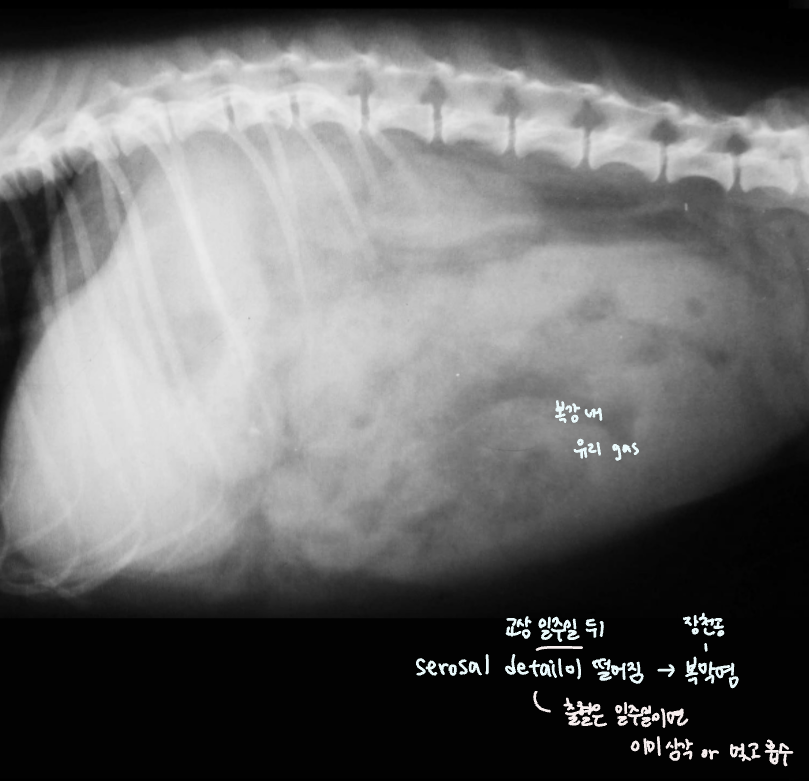

Serosal detail

- Serosal detail์ด ๋จ์ด์ง๋ฉด fluid๊ฐ ์ฐผ๋ค๋ ์๋ฏธ

- Transudate : ์ฐ์ฌ๋ถ์ , ๊ฐ๋ถ์ , hypoalbuminemia/proteinemia^[์กฐ์ง ์ผํฌ์์ด ๊ฐ์ํ๋ฉด์ ๋น ์ ธ๋์ฌ ์ ์์]

- Pus : peritonitis โ trauma, pancreas

- Blood : ๊ต์(ํํ์ฅ๊ธฐ์ ํ์ด), neoplasia, HBC

- Urine : pelvic fx๋ฅผ ๋๋ฐํ HBC

Intestinal perforation (์ฅ์ฒ๊ณต)

- ๋ฐ์ด, ๊ตฌํ , ๊ธฐ๋ ฅ์ ํ, depression ๋ฑ์ผ๋ก ๋ด์, 1์ฃผ ์ ๊ต์ history.

- ์ฅ์ฒ๊ณต โ ๋ด์ฉ๋ฌผ ๋น ์ ธ๋์ด โ ๋ณต๋ง์ผ์ผ๋ก ์งํํ ๊ฒ. (1์ฃผ์ผ์ด๋ฉด ๋ณต๋ง์ผ์ผ๋ก ์งํํ๊ธฐ ์ถฉ๋ถ!)

- ๋ฐฉ์ฌ์ ์ serosal detail ์ ํ (๋งค์ฐ ์ฌํ ์ผ์ฆ), ๋ณต๊ฐ ๋ด ์ ๋ฆฌ gas ๋ง์.